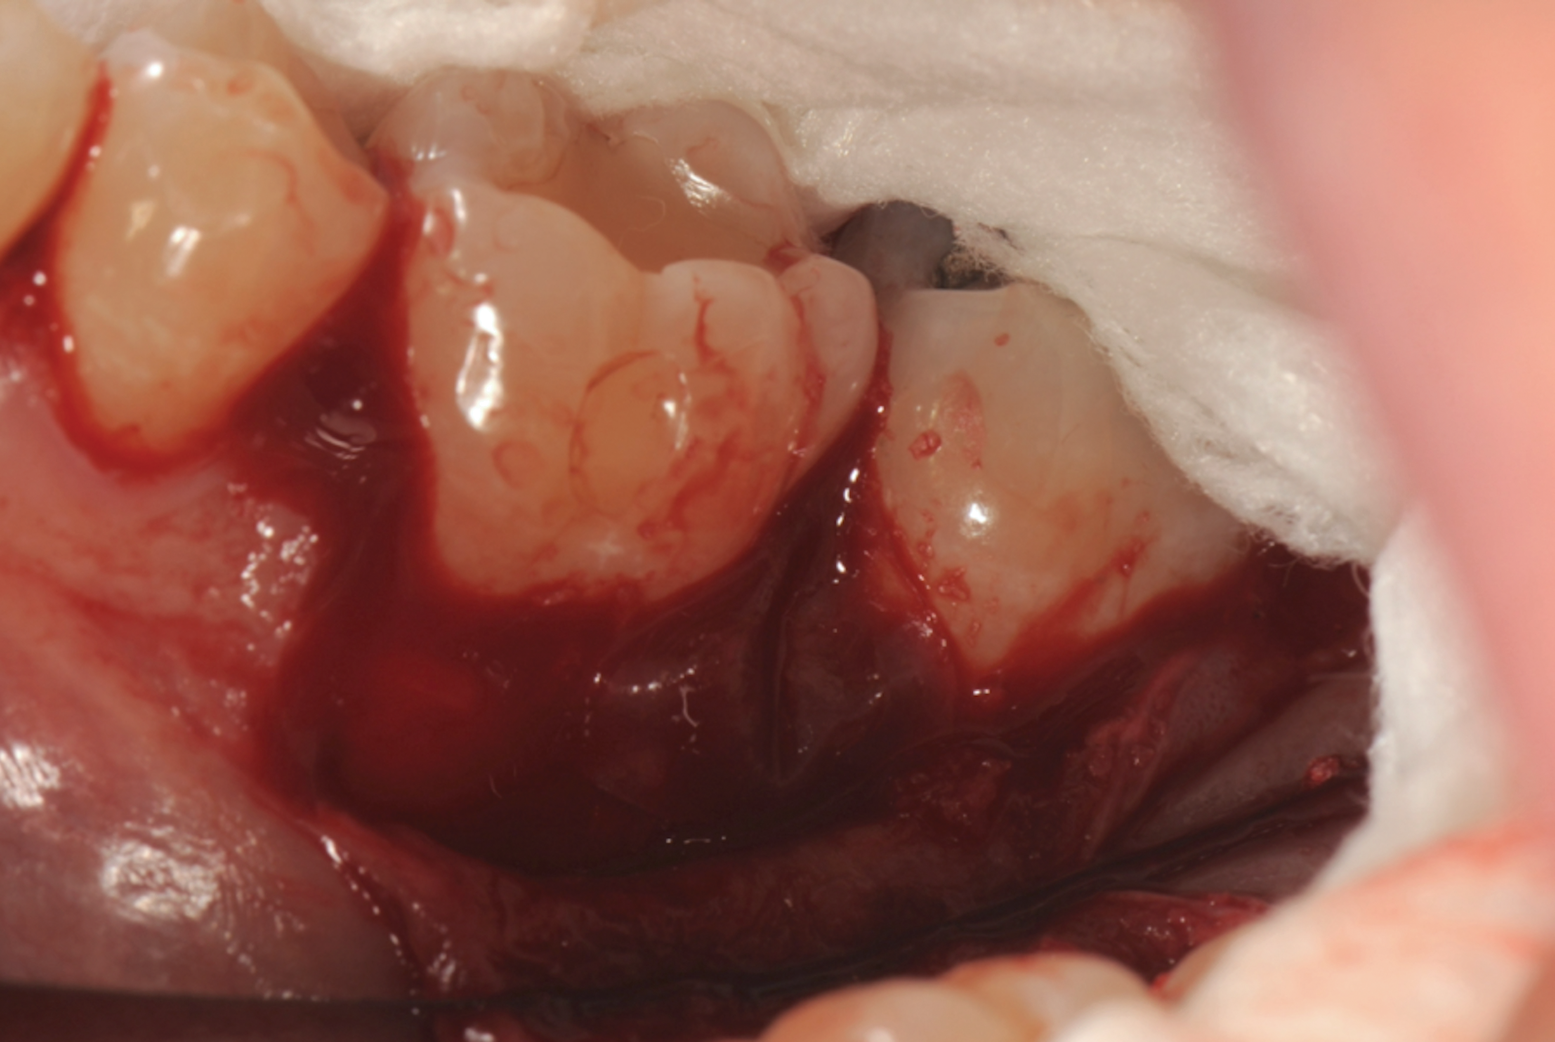

Fig 5. Surgical access and root preparation. The flaps were elevated after intrasulcular incisions were made and a releasing incision was done in the mesial aspect of tooth No. 19. The granulation tissue was removed.

Figure 5

Fig 6. 5-mm-deep distal intrabony defect at tooth No. 19.

Figure 6

In the present case, intrasulcular incisions were performed, followed by a releasing incision in the mesial aspect of tooth No. 19. A full-thickness flap was elevated in the buccal and lingual aspects (Figure 5 and Figure 6) using a minimally invasive periosteal elevator. The site was carefully managed to avoid salivary contamination.